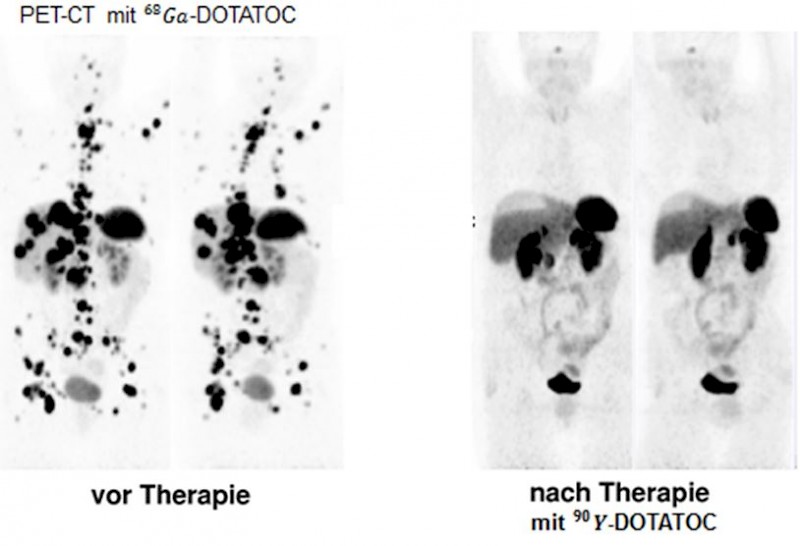

- Ga-68-DOTATOC zur Darstellung endokriner Tumoren

- Tumordiagnostik bei endokrinen Tumoren mit -DOTATOC: Die PET-CT ist bei der Diagnostik von endokrinen Tumoren der konventionellen Szintigraphie deutlich überlegen.